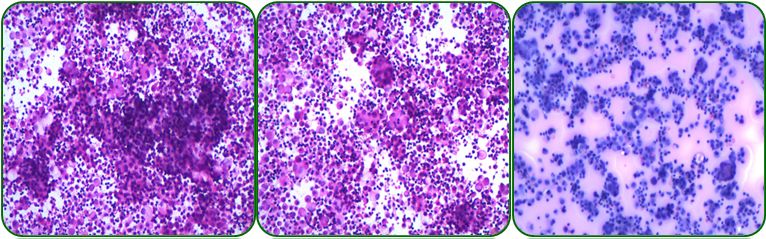

腹水培养及找肿瘤细胞未见异常,如图4。

图4 腹水脱落细胞学检查